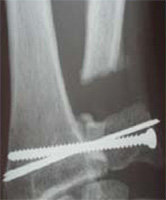

Le traitement d’un cal vicieux du poignet consiste le plus souvent en une ostéotomie, c’est-à-dire que l’on coupe le radius au niveau de la déformation, qu’on remet l’os en place dans un alignement normal et que l’on fixe cet os par du matériel qui est soit une plaque, soit une série de broches.Suivant la solidité du système, on met un plâtre pour cinq semaines ou on permet une mobilisation douce dès la première semaine. Dès que la consolidation est affirmée par les radios, on peut entreprendre une rééducation pour regagner le maximum de mouvements.Parfois, les troubles ne portent que sur la prono-supination et l’intervention porte alors seulement sur l’ulna : raccourcissement par résection (opération de Darrach ou vissage des deux os, en enlevant un cylindre d’os pour permettre le mouvement (intervention de Sauvé-Kapandji).

![]() |

|

Ostéotomie avec ostéosynthèse |

Intervention de Sauvé-Kapandji |